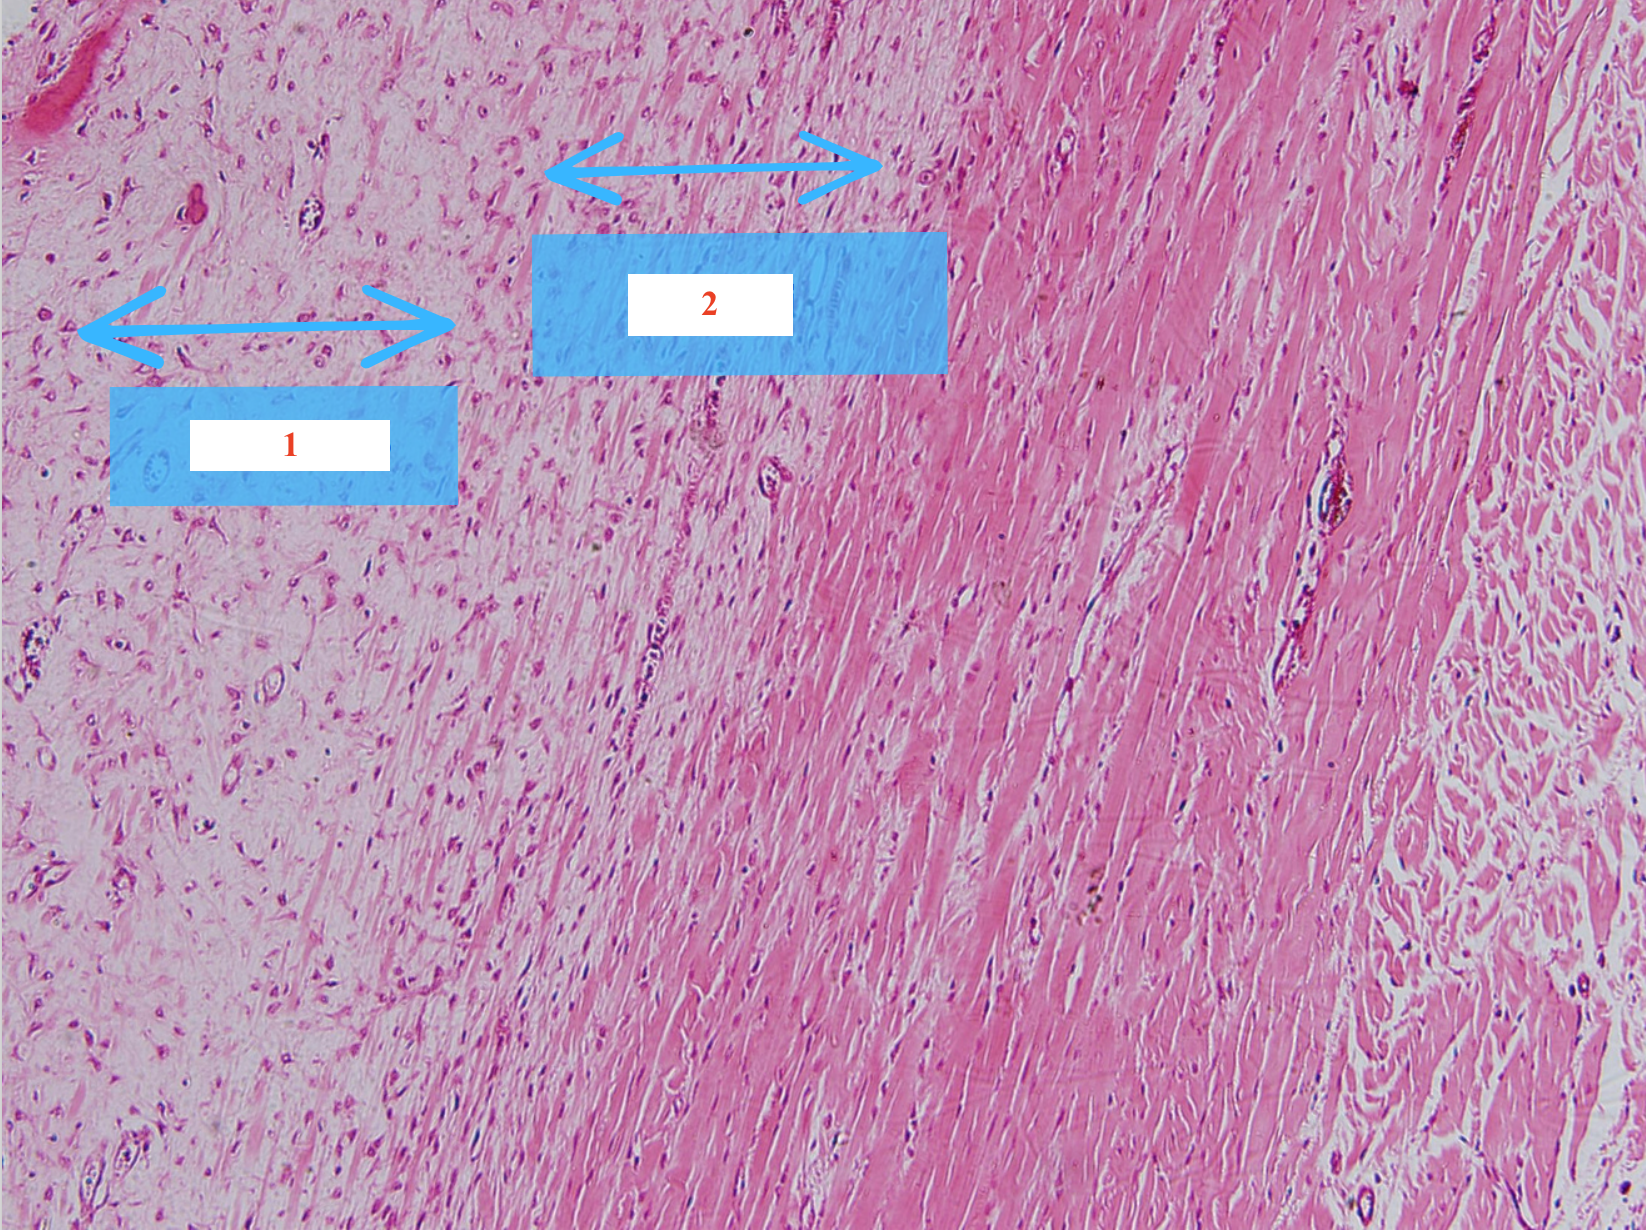

Cấu trúc gì ? (số 1 + 2)

Tế bào gì (số 3)

Khoang Henlé

Đĩa nối

Nhân tế bào cơ tim

Cấu trúc gì ?

Cơ tim cắt dọc